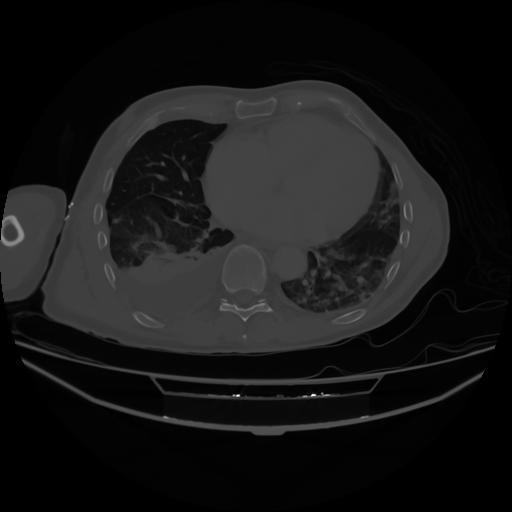

4 CUERPO,CE,Axial,3.0,CUERPO,,